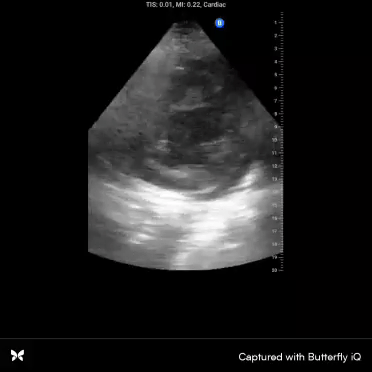

Anyone recognize this structure? I’ve never gotten such a nice picture of it before…

(Hint, it’s not a cardiac structure. If you turn the probe to the right you’ll see the aorta, which is not seen in this image)

tiny image...thoracic vertebra and sc.